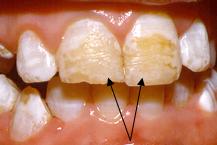

2 Capa amarilla u opacidad marrón del emsalte

• Diagnóstico diferencial con fluorosis. Las fluorosis leve suele mostrar estas características